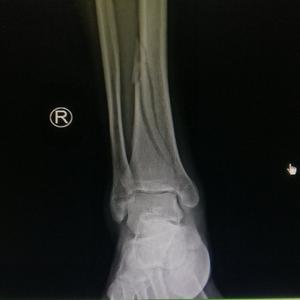

脛骨 骨折 手術 痛み- 骨折日記4:手術 人口骨とチタンプレートの埋込 脛骨高原骨折 バイク, 脛骨高原骨折 5月7日の日曜に入院し、12日金曜に手術となりました。 整形外科の手術が多いらしく、時間は12時から13時くらいの間に開始、前のオペが終わり次第ということ 足首の骨折の症状とは? 歩けるまでに手術やリハビリが必要? 17/8/15 17/8/16 骨・関節・筋肉の不調 スポーツをしている人でなくても、ちょっとした段差でつまずいたり、思わぬ転倒などが原因で、足首や足関節を骨折してしまうことがあります。 捻挫

骨折から1年と1か月、とうとうプレートとボルトを抜く抜釘手術を受けてきました。 骨折の経緯は下記 アイスクライミングで右足果部 腓骨・脛骨骨折 復帰までの記録 ①受傷から手術~退院まで ムカデのおにいさんのブログ アイスクライミングで右足果部腓骨・脛骨骨折 復帰までの記録ずれがない骨折であれば、ギプス装着を数週間行うことで治癒することが多いとされています。 手術 骨のずれが大きいなどの場合には、骨の位置を正しい位置に戻す手術が必要です。 足関節の骨折では、骨片の配置を正しく整え、また治癒中に再び骨片がずれることのないよう、観血的整復固定術(ORIF)と呼ばれる手術を行うことがあります。 患部を切開して、折れた骨を適切な位置に戻し 骨折手術の方法 骨折手術には種類が複数あり、状態によって手術法が異なります。 ・ピンニング 折れた骨同士を挿入したピンで固定する方法で、骨が折れたことでずれた場合などに使用されます。 ・スクリュー固定 ネジで骨折部を止める方法で、ピンニングと同じく比較的単純な骨折の場合に使用されます。 ・プレート固定 骨折した部分をスクリューとプレートで固定させる方法です

脛骨天蓋骨折 足関節の機能障害を防ぐためにも正確な整復が必要となります。 このため、偏位がまったくない軽微な骨折であればギプス固定などの保存的治療を行いますが、多くはネジやプレートを使用して偏位部を整復し固定する手術が必要となります。 また、粉砕が激しく、正確に整復できない場合には、欠損部分に自分の腸骨の一部や人工骨を移植することもあります。 強固に脛骨骨折高原骨折の場合、 手術療法 が適応となるのは、 以下のような場合であると言われています。 ・転位型である ・脛骨関節面が5mm以上の陥没している 加えて、年齢や生活スタイル、体力や既往歴などから総合的に判断して、 手術療法の適応となります。 代表的な手術療法の方法としては、 ・Bookopen法(関節切開法) ・関節鏡視下法 があります。 Bookopen法(関節切開法) Book